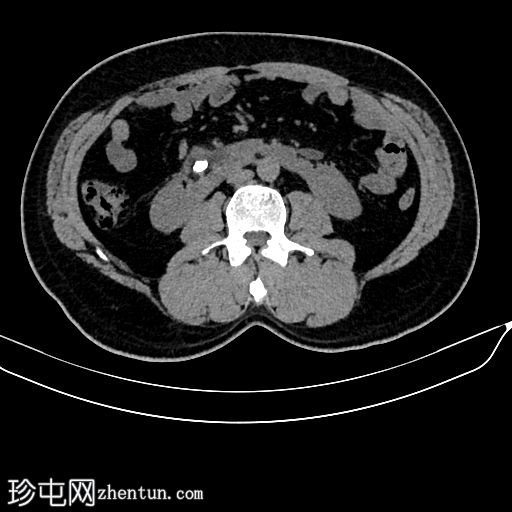

CT

轴位

平扫

双肾位置低于正常,位于肠系膜下动脉下方,位置更偏内侧,下极在腹主动脉前方中线处融合。

肾皮质厚度及强化均正常。

双侧肾盂朝向前方。

右侧肾盂轻度扩张,伴有结石。